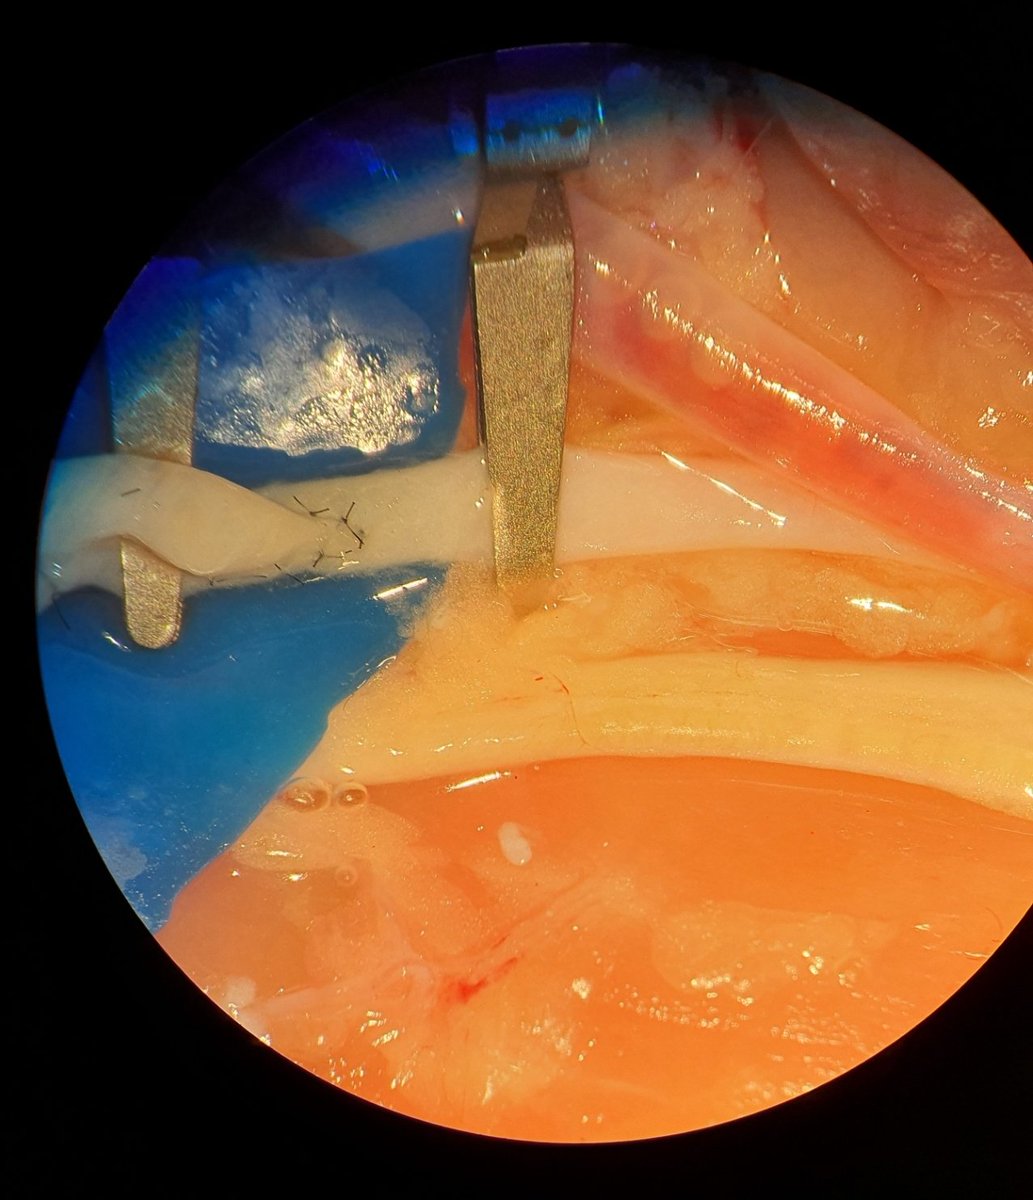

🧠 Der 1. Preis als bester Nachwuchswissenschafter geht an Eric Freund von der Universitätsklinik für #Neurochirurgie der #MedUniWien. Wir gratulieren zur Auszeichnung der ÖGNC! Details zur Arbeit zur Verbesserung der #Therapie von malignen #Hirntumoren ⬇️ bit.ly/3YPO6fC